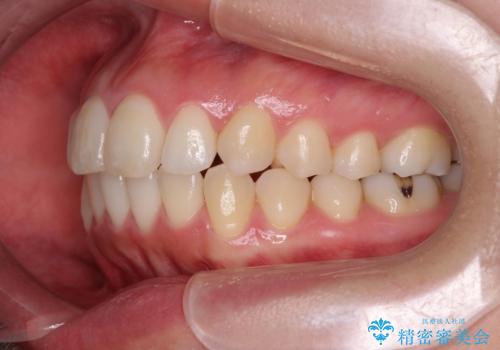

上下の歯は、上顎の歯が相対的に前に位置する咬合関係で押し出されるように前歯に角度がついている状態です。

咬合関係の改善、前歯の角度、がたつきを改善するため、マイクロインプラントを用いて上顎の奥歯を後方へ移動させていきます。